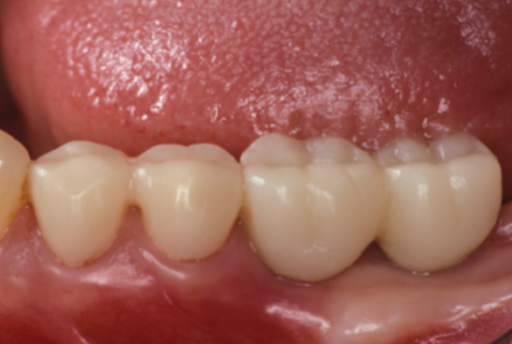

| 主訴 | 全顎治療希望、歯が無いので噛みずらい。定年で時間の余裕出来たので、インプラントで治療して欲しい。 |

| 治療内容 | プラークコントロール不良なため歯周治療を行い、残存歯を極力温存し、欠損部インプラントを施し咬合再構成を行う。 プロビジョナルレストレーションによる咬合関係を模索した後、全顎にわたりセラミックによる補綴治療、その後メインテナンスに移行 |

| 治療費 | 6,470,000円(税込)(インプラントすべて含む) |

| 治療期間 | 1年6ヶ月 |

| 治療回数 | 72回 |

| 想定されたリスク | 食いしばり(パラファンクション)によるセラミックの破折、歯の破折 |